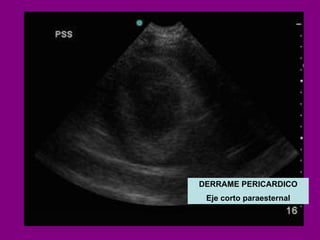

DERRAME PERICARDICO Eje corto paraesternal